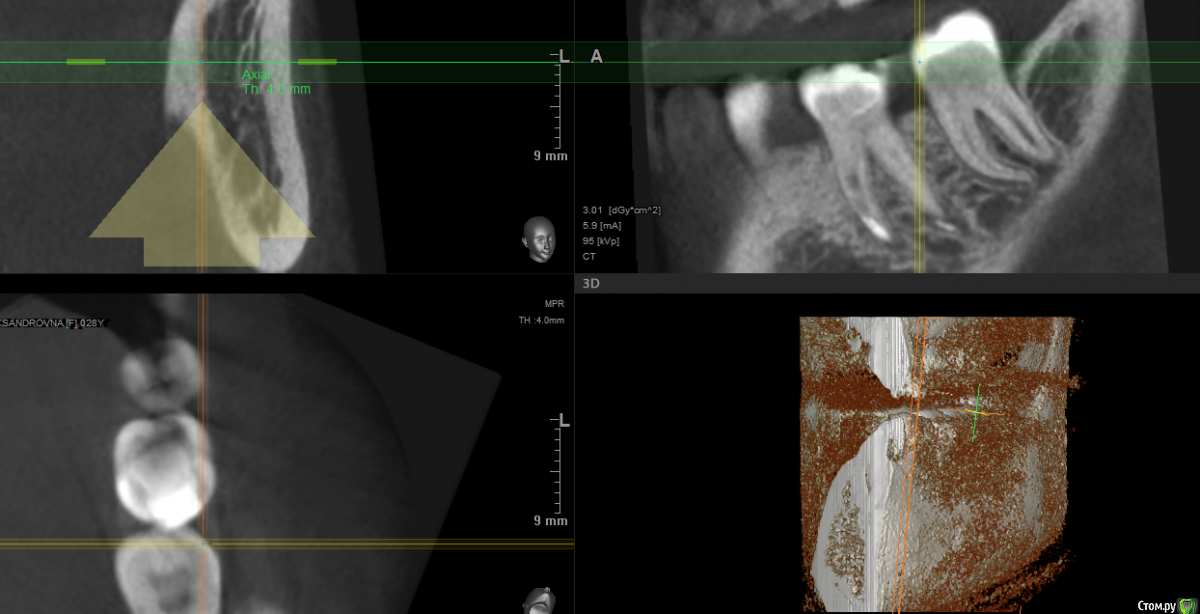

В общем, сходила я в другую клинику, сделали рентген, посмотрели, выписали антибиотики, дали месяц зубу, коронку на него нельзя, и по их словам даже если выживет, то около года протянет. На сегодняшний день, изменения не особо: в определенном смыкании боль осталась, бывает даже от прикосновения к зубу, не сильная, либо я за полгода лечения привыкла к ней. На днях сделала 3д снимок, хотелось бы узнать мнение профи: делать имплант, одноэтапный? надо наращивать кость? или всё же ещё раз перелечить зуб?

post-57643-0-56729500-1555936944_thumb.png